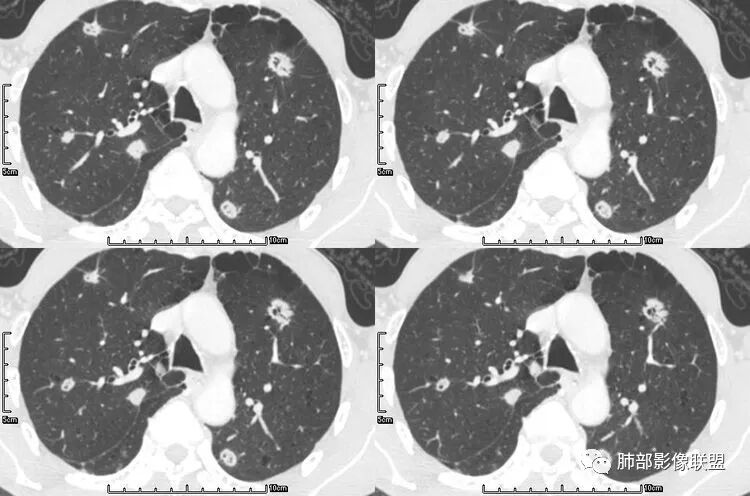

老年男性,咳嗽,咳痰带血2月,左下肺可见一团块影,深分叶,胸膜牵拉,可见坏死,坏死边界清,考虑恶性,双肺多发散在结节影,可见分叶,空洞,胸膜牵拉,考虑转移瘤;

患者老年男性,咳嗽、咳痰、痰中带血伴胸闷2月余。长期大量吸烟史。查肝肾功能、血糖、血脂、心肌酶、电解质、血沉、C反应蛋白、抗“O”、类风湿因子、抗核抗体谱无明显异常。肿瘤标志物提示NSE、CYFRA21-1稍升高。胸部CT:肺气肿背景,左肺下叶后基底段不规则肿块影,见支气管截断,内见大片状低密度区及部分血管影,增强轻度强化,远端空洞形成。双肺多发不规则实性结节影、见毛刺、胸膜牵拉及血管集束,结节内见空洞形成,部分可见血管影,多位于胸膜下。双肺见多发肺大泡。综合考虑左下肺恶性病变并双肺转移。鳞癌或淋巴瘤可能。鉴别血管炎性病变及真菌感染。

张延军:双肺多发结节,空洞影,后者洞壁厚薄不均匀,部分腔内丝丝落落,呈分叶征,边缘见毛刺影,病灶大部分位于胸膜下,与血管相连,右肺下叶前基底段结节近段支气管截断,远端见空腔。左肺下叶病灶密度不均,背段支气管壁增厚,管腔狭窄。考虑1.双肺下叶占位性病变伴肺内空洞性转移 2.多原发的占位 3.肉芽肿性血管炎代排。

南边:我们再看看左下叶背段的病灶

本病例左肺下叶肿块,有深分叶、毛刺、胸膜牵拉凹陷、支气管截断及纵隔内淋巴结肿大等征象,都均支持病灶为恶性,如腺癌,而且叶间裂的多发结节也提示是腺癌来源可能大;双肺多发结节、肿块,大部分病灶有分叶、毛刺及胸膜凹陷的恶性征象,与原发肿瘤本身的性质有关,所以应该与左肺下叶肿块同源,而且双肺多发病灶内空洞也具有多样性;

此病例中空洞形态多样,内壁不光整,有分隔影,周围未见明显卫星灶及钙化灶,结核不太符合;患者病史慢性病史,无明显发热,缺乏中毒临床表现,急性感染基本排除;各种中性粒细胞胞浆抗体阴性,没有鼻窦炎,肾脏等病史,基本排除血管炎;霉菌性空洞常见于免疫机能低下者, 常为空洞、肺炎、伴“ 晕圈”征的结节及支气管扩张合并存在。